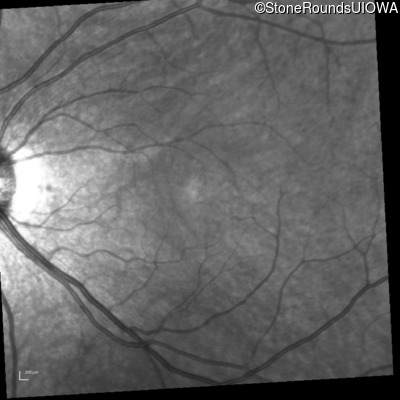

Infrared Fundus Photograph - Right - 20/40 +1

Exemplar